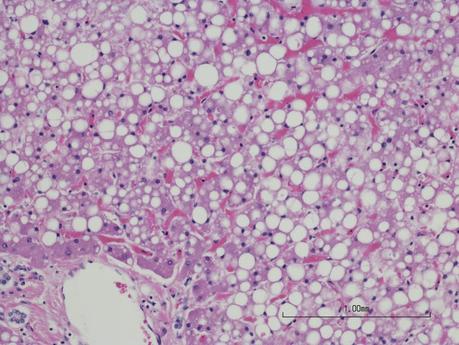

Chinese researchers have demonstrated that variants of the gut bacteria Klebsiella pneumoniae may contribute to fatty liver. The bacteria convert carbs from food into alcohol, which in turn causes production of fat in the liver. This discovery might contribute to explaining why a keto diet leads to less deposition of fat in the liver.

Initially, the doctors gave the patient medication for intestinal fungi, which did not help. However, they were able to isolate the alcohol-producing variants of the bacteria Klebsiella pneumoniae from the patient's intestines. When they inserted these bacteria into mice, the mice also developed fatty liver.

When the researchers thereafter compared people with and without fatty liver, they discovered that 60 percent of those with fatty liver had alcohol-producing Klebsiella pneumoniae in their gut. The corresponding number for those without fatty liver was around 6 percent.